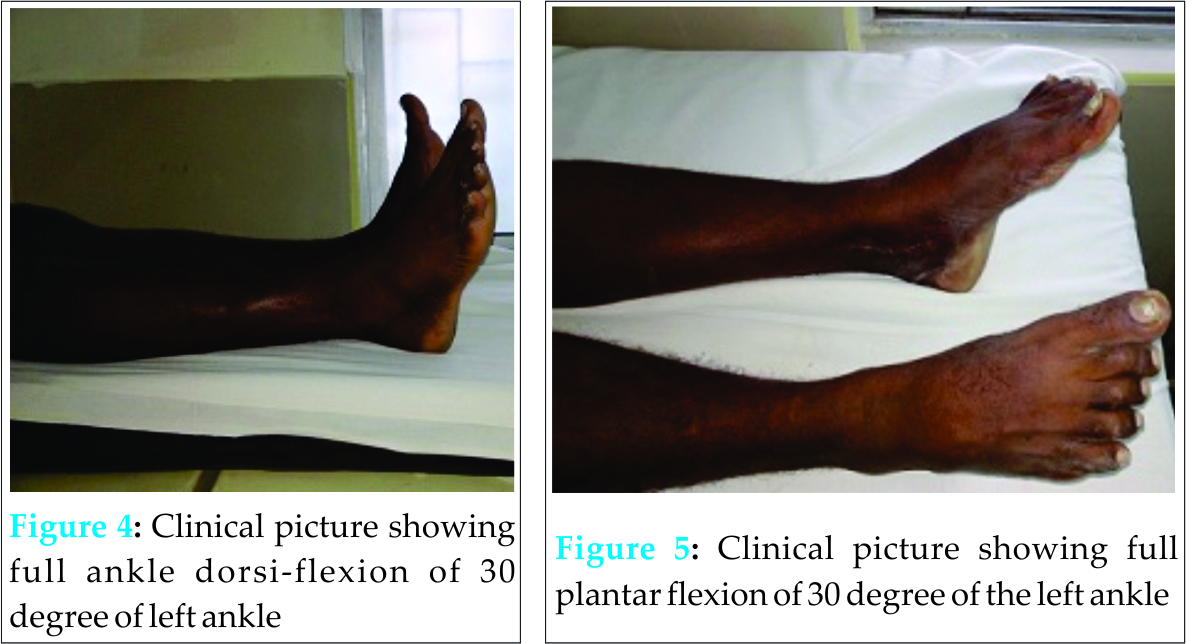

All 11 patients were followed up till the end of the study. Ten of the 11 patients went on to union at an average of 13.8 weeks (range 12-17 weeks). Patient No. 5 (Table1)had a comminuted fracture of the medial malleoli which was treated by tension band wiring which failed to unite with bone resorption seen on follow-up radiographs. She was a diabetic with a BMI of 31. She was offered a revision fixation with bone grafting but she refused for surgery. She was put on a Ankle-Foot Orthoses (AFO) and mobilized. Although she had satisfactory mobility with a walker support her functional outcome was poor. Four patients had a painful scar which improved at the end of 4 weeks. The two patients who had delayed wound healing and delayed suture removal were both females with BMI > 30 with diabetes. The functional ankle score was excellent in 6 [Fig 4 & Fig 5], good in 3, fair in one and poor in one.